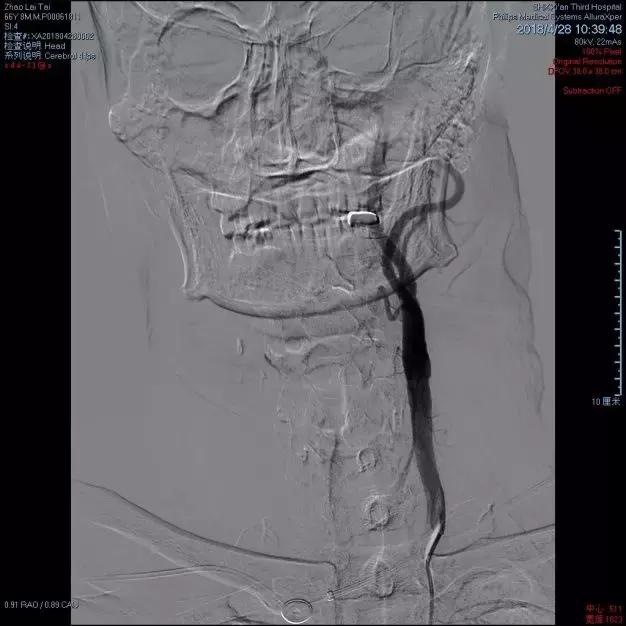

术前DSA检查示左侧颈内动脉重度狭窄